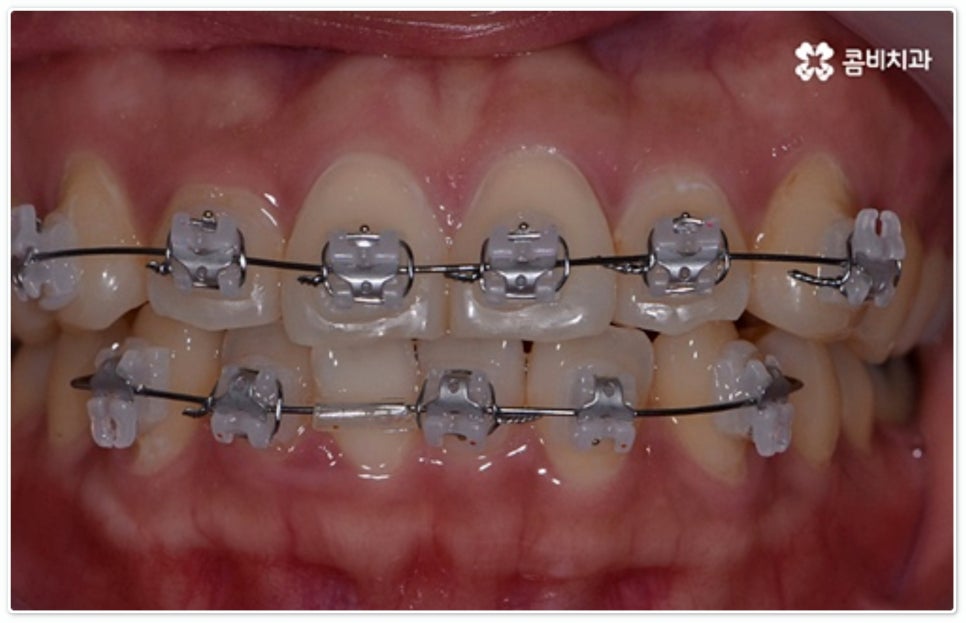

앞니부분교정 이란 전체 치아가 아닌 앞니만 타겟으로 하는 교정 치료를 의미하는 거예요. 즉 필요한 앞니 부분 6개의 치아에만 부분적으로 교정 장치를 장착해 치열을 고르게 만드는 방법으로, 12년 정도가 소요되는 전체 교정에 비해 38개월 정도로 비교적 짧은 기간 동안 진행하는 치료이기 때문에 통증과 불편이 적어 대다수의 환자분들이 선호하고 있어요. 또한 브라켓의 크기가 작아 이물감이 거의 없고 발음을 하거나 음식물을 섭취할 때도 보다 수월하다는 장점을 가지고 있는데요.

그렇지 않고 전후방 각도 조절 또는 단순 횡적인 움직임으로 치열 개선이 가능한 케이스는 부분 교정을 진행하는데, 사진에서 보시는 사례가 바로 그런 경우에 속하고 있습니다. 앞니 6개에만 브라켓을 부착하였는데 보시다시피 치아 색상과 유사한 세라믹 재질의 장치를 이용하여 심미성 또한 높여 주었음을 알 수 있어요.